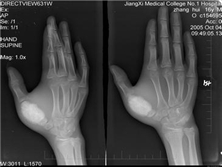

尤文氏肉瘤

尤文肉瘤(Ewingssarcoma)原发于骨髓的原始细胞,又称未分化网状细胞瘤...

X线平片